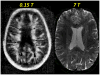

Magnetic resonance imaging (MRI) has led to the identification of widespread brain abnormalities in multiple sclerosis (MS) that extend far beyond the classic white matter lesion. These findings have generated the idea that MS should be understood as a disease of the whole brain, not just the white matter. While it is no doubt the case that many different pathways are ultimately involved in the destruction of brain tissue that occurs in MS, the implications of the accumulated evidence for understanding disease pathophysiology - and hence the overall significance of these imaging findings - are doubtful. Here, I argue that the principled use of imaging can, in fact, address questions about the genesis of these whole-brain abnormalities, rather than simply describe them.